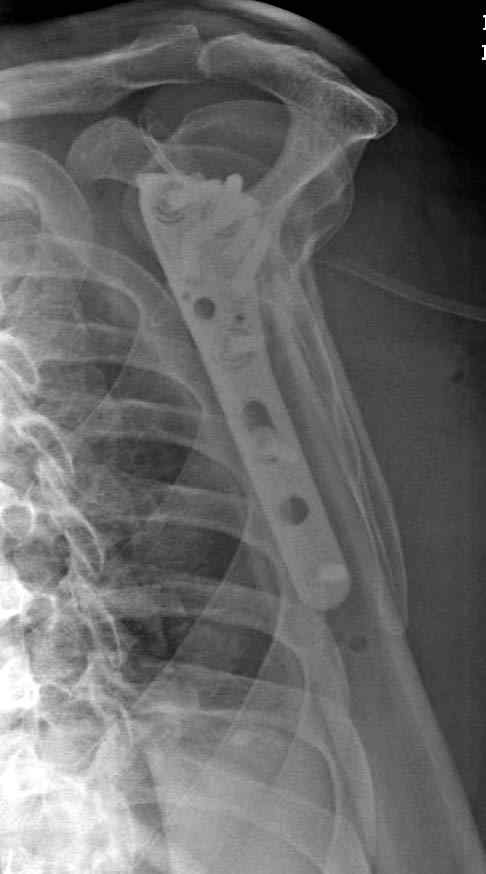

Рентгенограммы действительно с дефектом укладки, но интраоперационная репозиция, можете поверить, была удовлетворительная как в акcиальной, так и в сагиттальной плоскостях. Интраоперационная рентгенограмма прилагается, хотя укладка тоже на ахти. По тактике - разделяю Ваше мнение об отсутствии необходимости реостеосинтеза, а тем более об эндопротезировании, хотя это все было предложено пациентке ведущими ортопедами-травматологами России.

Здесь пример открытой репозиции 57 летнего с переломом плеча (1,2) смещение обнаружено на интероперационном снимке. При нормальной прямой проекция (3) угловое смещение обнаружили в аксиальной проекции (4)

После устранения смещения пластина установлена выше (5,6,7) и финальные снимки (8,9,10)